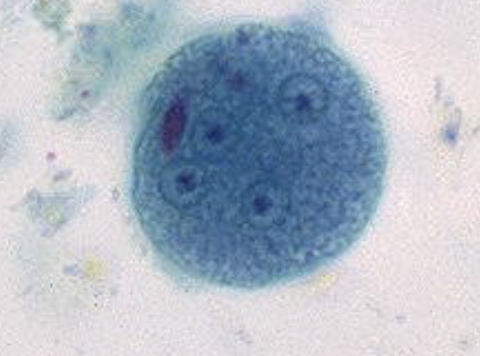

Entamoeba coli

E. coli troph form

E.coli troph form

What parasite has splintered chromatoidal bars and may contain glycogen vacuoles and has up to 8 nuclei?

E. coli

E. coli cyst

E.coli cyst